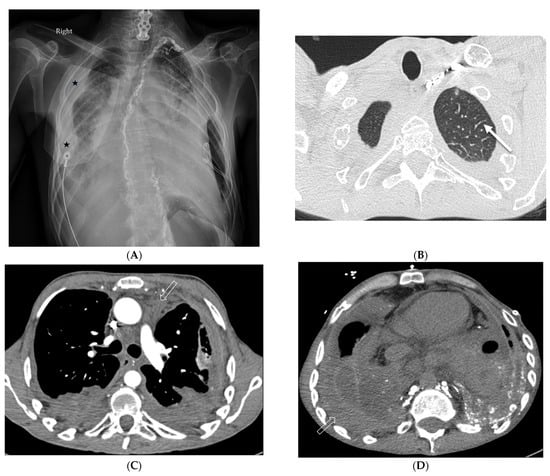

8.1. Diffuse Alveolar Hemorrhage (DAH)

8.2. Granulomatous–Lymphocytic Interstitial Lung Disease (GLILD)

8.3. Granulomatosis with Polyangiitis (GPA)

8.4. Erdheim Chester Disease (ECD)